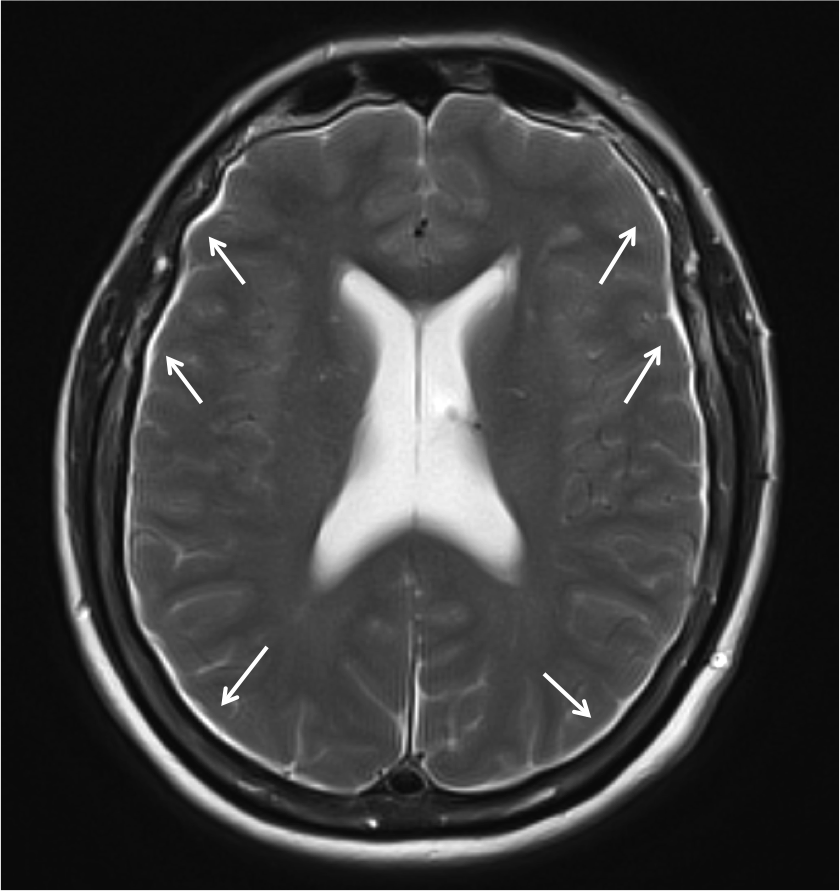

En la Imagen 2, se observan los higromas subdurales por disminución de la presión de LCR. En otras ocasiones, se pueden producir hematomas subdurales por rotura de las venas puente.